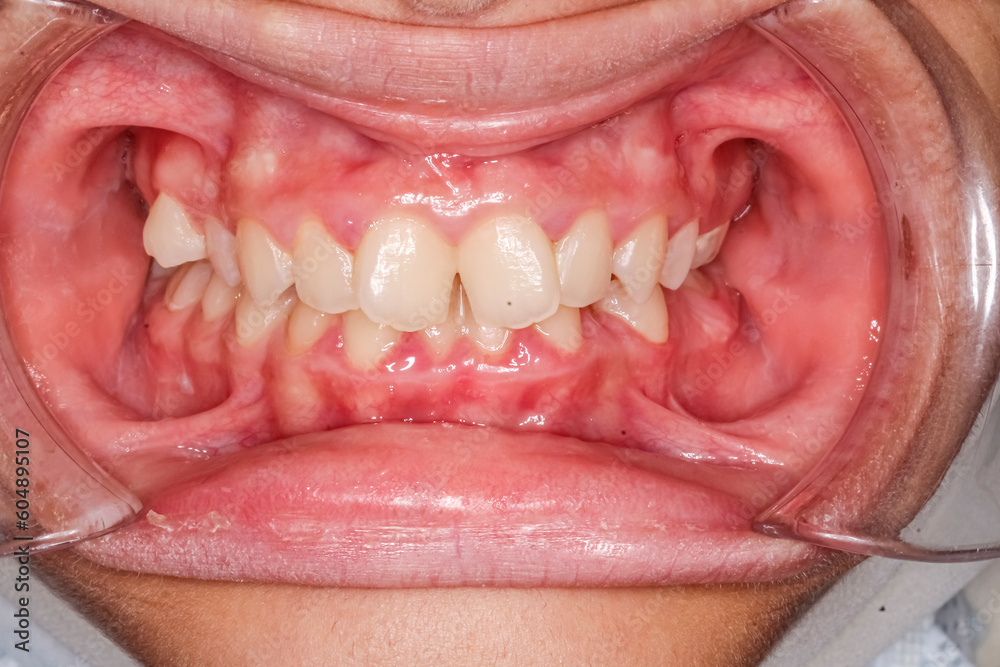

From stock.adobe.com

Dental maxillary and mandibular arches in occlusion with biting teeth Misaligned Teeth Causing Cheek Biting There are several different types of misaligned bites, also called malocclusions. Malocclusions are responsible for a number of different dental health symptoms people may experience due to. Malocclusion is the most common reason for referral to an orthodontist. Malocclusion is the medical term for a bad bite, where someone’s teeth are misaligned and don’t make proper contact. Uneven jaw occurs. Misaligned Teeth Causing Cheek Biting.